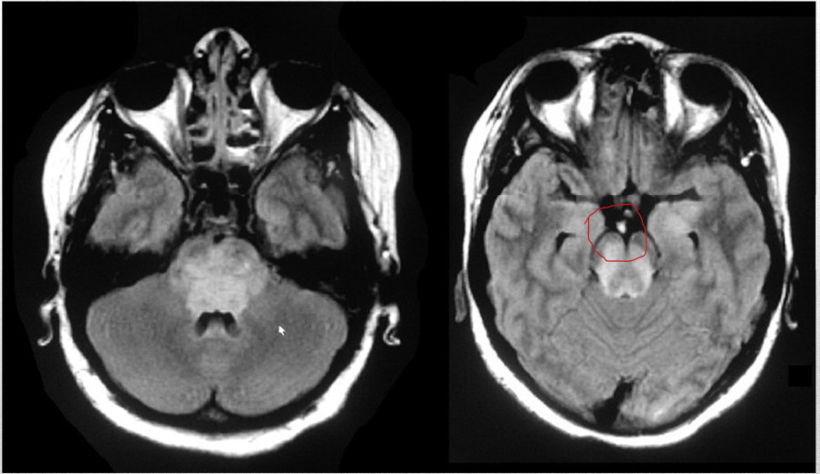

this infarct is a small lesion less than 5mm in diameter. found in short penetrating arterioles of basal ganglia, pons, cerebellum, internal capsule/ assoc with uncontrolled HTN, DM.

lacunar infarct

this infarct leads to thalamic syn leading to c/l hemisensory disturbances followed by the development of spontaneous pain and hyperpathia (exaggerated levels of pain). pts usually have macular sparing homonymous hemianopia

PCA infarct

basilar artery infarct

occlusion of these arteries leads to vertigo, n/v, nystagmus, ipsilateral limb ataxia, and contralateral spinothalamic sensory loss of the limb. if massive infarction occurs then this can lead to coma, tonsillar herniation and death

cerebellar artery infarct